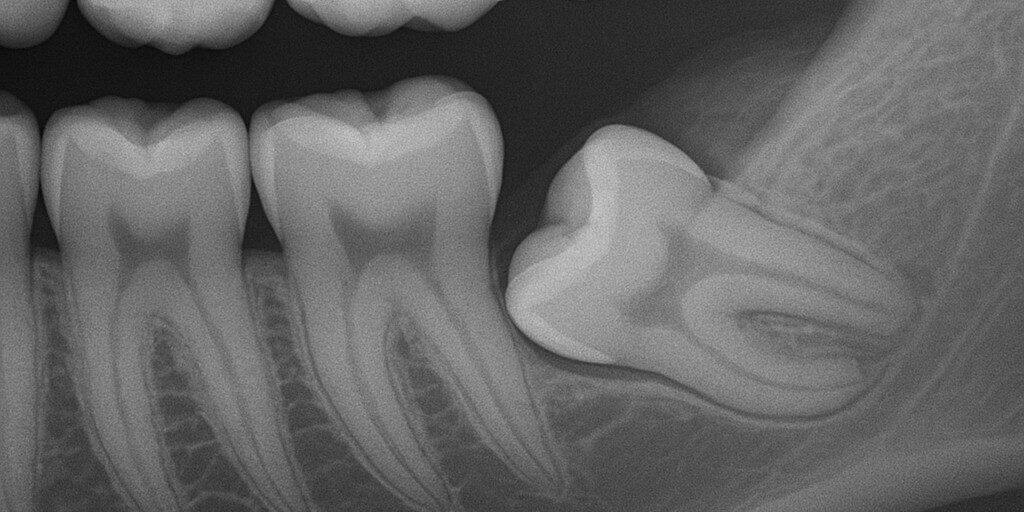

In base all’angolazione rispetto all’asse del secondo molare:

Verticale

Mesio-angolato

Disto-angolato

Orizzontale

Radiografia panoramica (ortopantomografia): permette di valutare la posizione del dente, la sua inclinazione, la vicinanza al nervo alveolare inferiore e la presenza di lesioni cistiche.